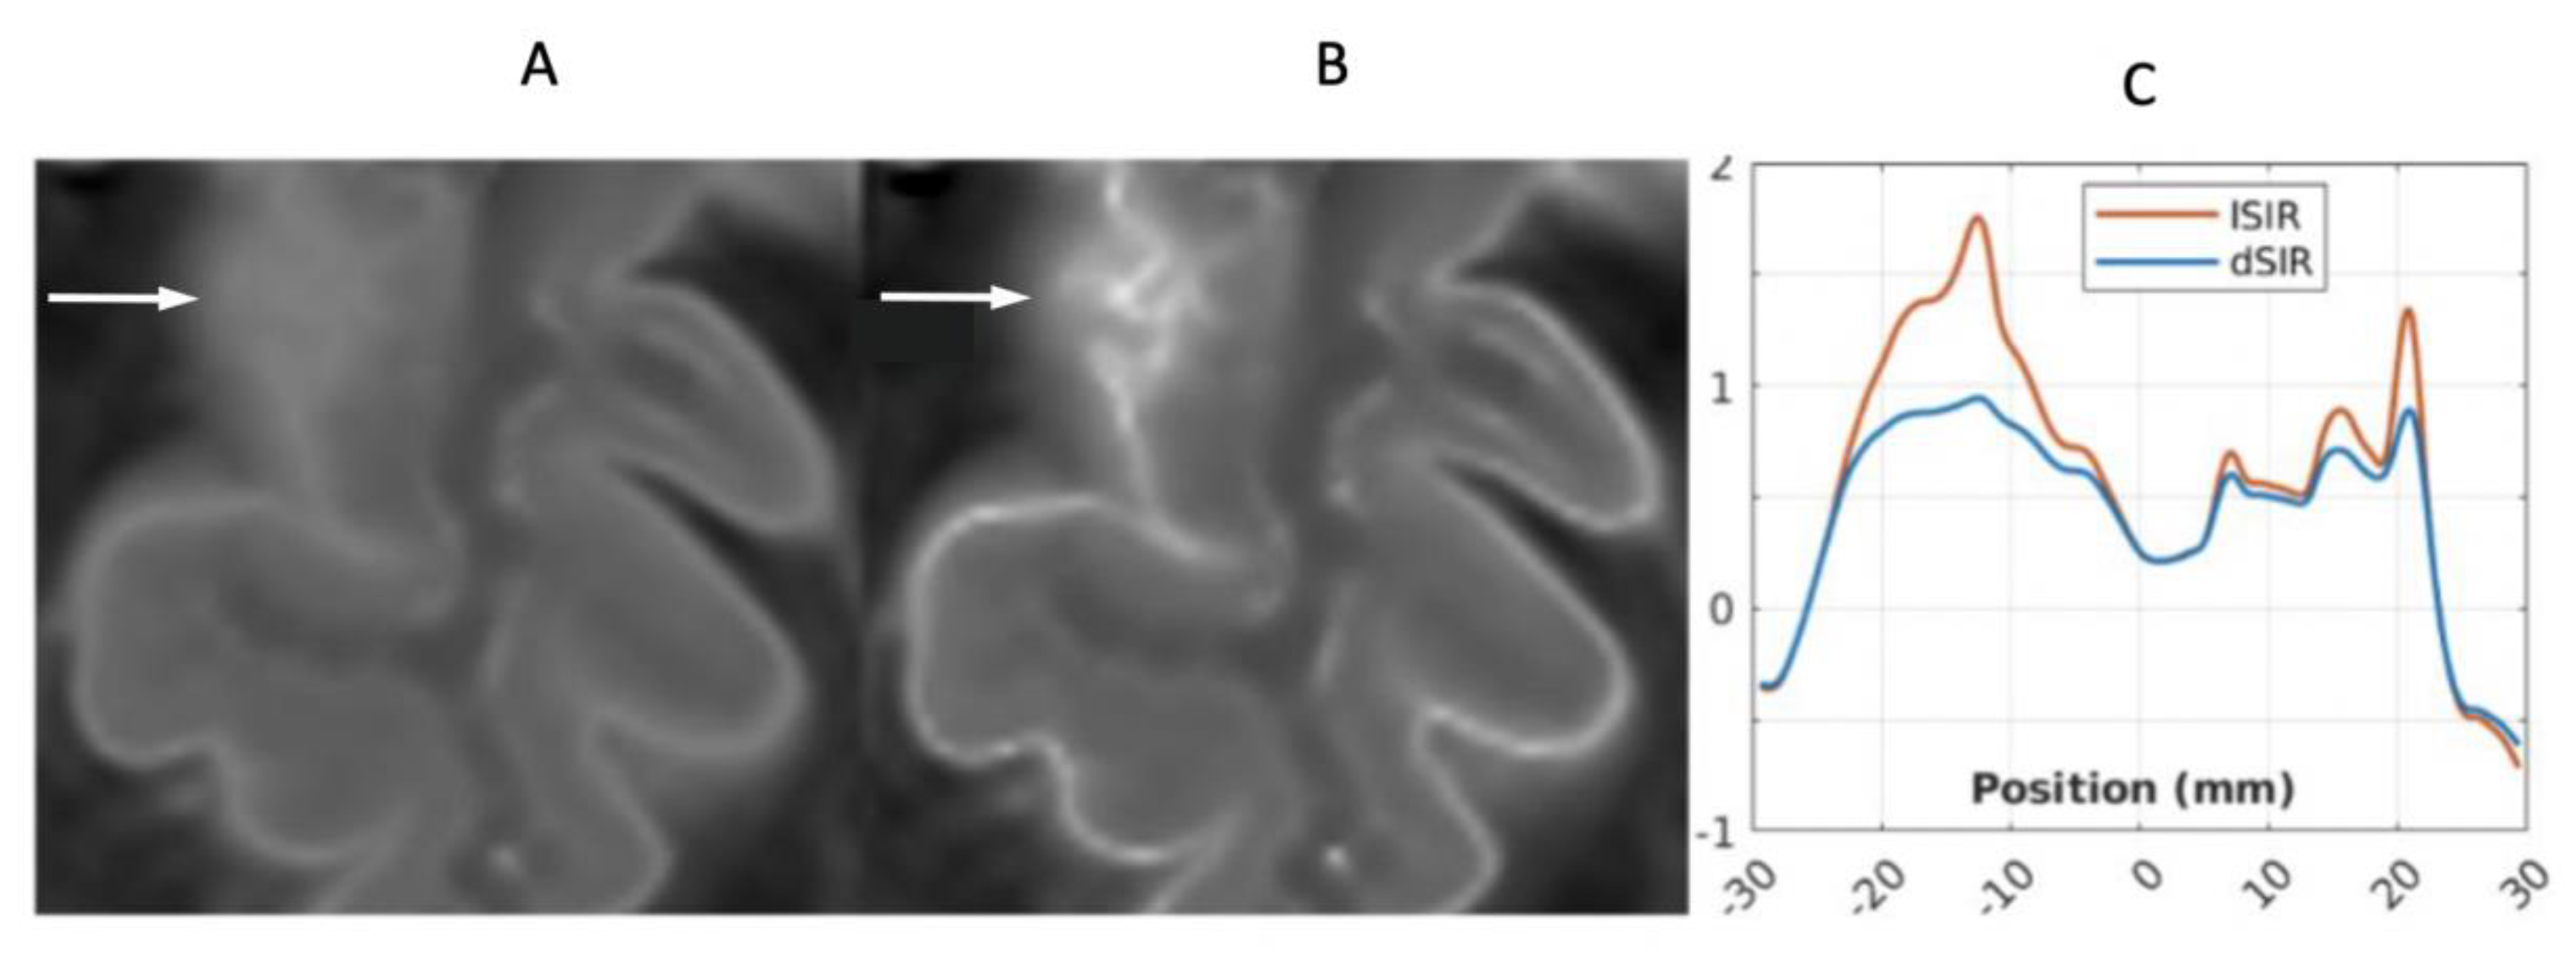

- Ultra-high contrast MRI using bipolar filters (BLAIRs) can show abnormalities with very high contrast where little or no change from normal is seen with common conventional state-of-the-art sequences.

- The abnormalities shown with ultra-high contrast are due to small changes in tissue properties such as T1 and T2 in disease. This is complementary to existing sequences which show abnormalities due to larger changes in T1 and T2 in disease.

- At boundaries between tissues and fluids on ultra-high contrast images there is frequently an increase in contrast and an increase in the spatial resolution of that contrast.